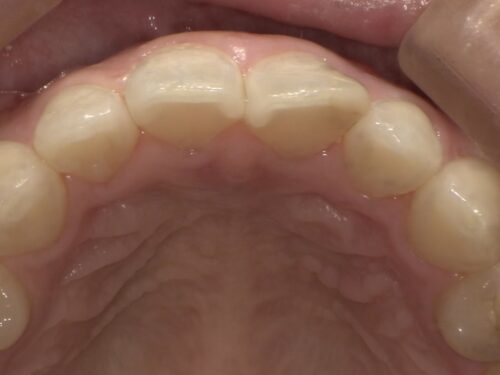

真正面だけでなく、

横から見たり、

噛む面から見たりと、この詰め物の状態をよく確認します。

また、

レントゲンでも詰め物の奥で再びむし歯になっていないか等、

色以外にほかに問題点がないか検査が必要です。

今回はとくに問題ありませんでした。